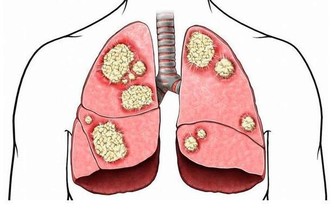

肺臟排毒

蘿蔔是肺臟的排毒食品:在中醫眼中,大腸和肺的關係最密切,肺排出毒素程度取決於大腸是否通暢,蘿蔔能幫助大腸排泄宿便,生吃或拌成冷盤都可以。

百合提高肺臟抗毒能力:肺臟向來不喜歡燥氣,在燥的情況下,容易導致積累毒素。蘑菇、百合有很好的養肺滋陰的功效,可以幫肺臟抗擊毒素,食用時加工時間不要過長,否則百合中的汁液會減少,防毒效果要大打折扣。

排汗解毒:肺管理皮膚,所以痛痛快快地出一身汗,讓汗液帶走體內的毒素,會讓我們的肺清爽起來。除了運動以外,出汗的方法還可以是熱水浴,浴前水中加一些生薑和薄荷精油,使汗液分泌得更暢快,排出身體深處的毒素。

深呼吸:每次呼吸時,肺內都有殘餘的廢氣無法排出,這些廢氣相對於那些新鮮、富含氧氣的空氣來講,也是一種毒素。只需幾個深呼吸,就能減少體內廢氣的殘留。

肺臟最佳排毒時間:肺臟最強的時間是早7點~9點,此時最好能夠通過運動排毒。在肺最有力的時候進行慢跑等有氧運動,能強健肺排出毒素的功能。